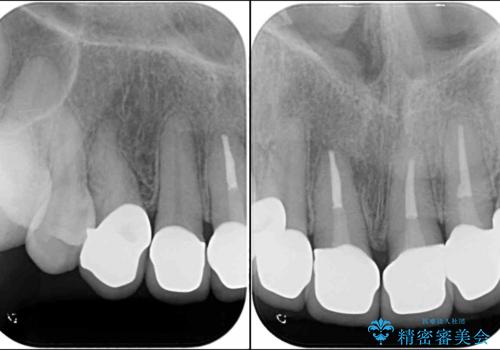

- 前歯の歯肉の高さが左右で異なっていることを気にして来院された患者様です。

歯肉レベルを調整するために歯周外科処置をおこない、その後にオールセラミッククラウンにて補綴することとしました。

歯肉の位置を整えるには歯周外科処置が必要であると説明した際には、なかなか踏み切ることができず、大変悩まれていました。

処置後の痛みはあまり気にならず、歯肉位置の左右差もほとんどなくなり、患者様には大変満足していただきました。